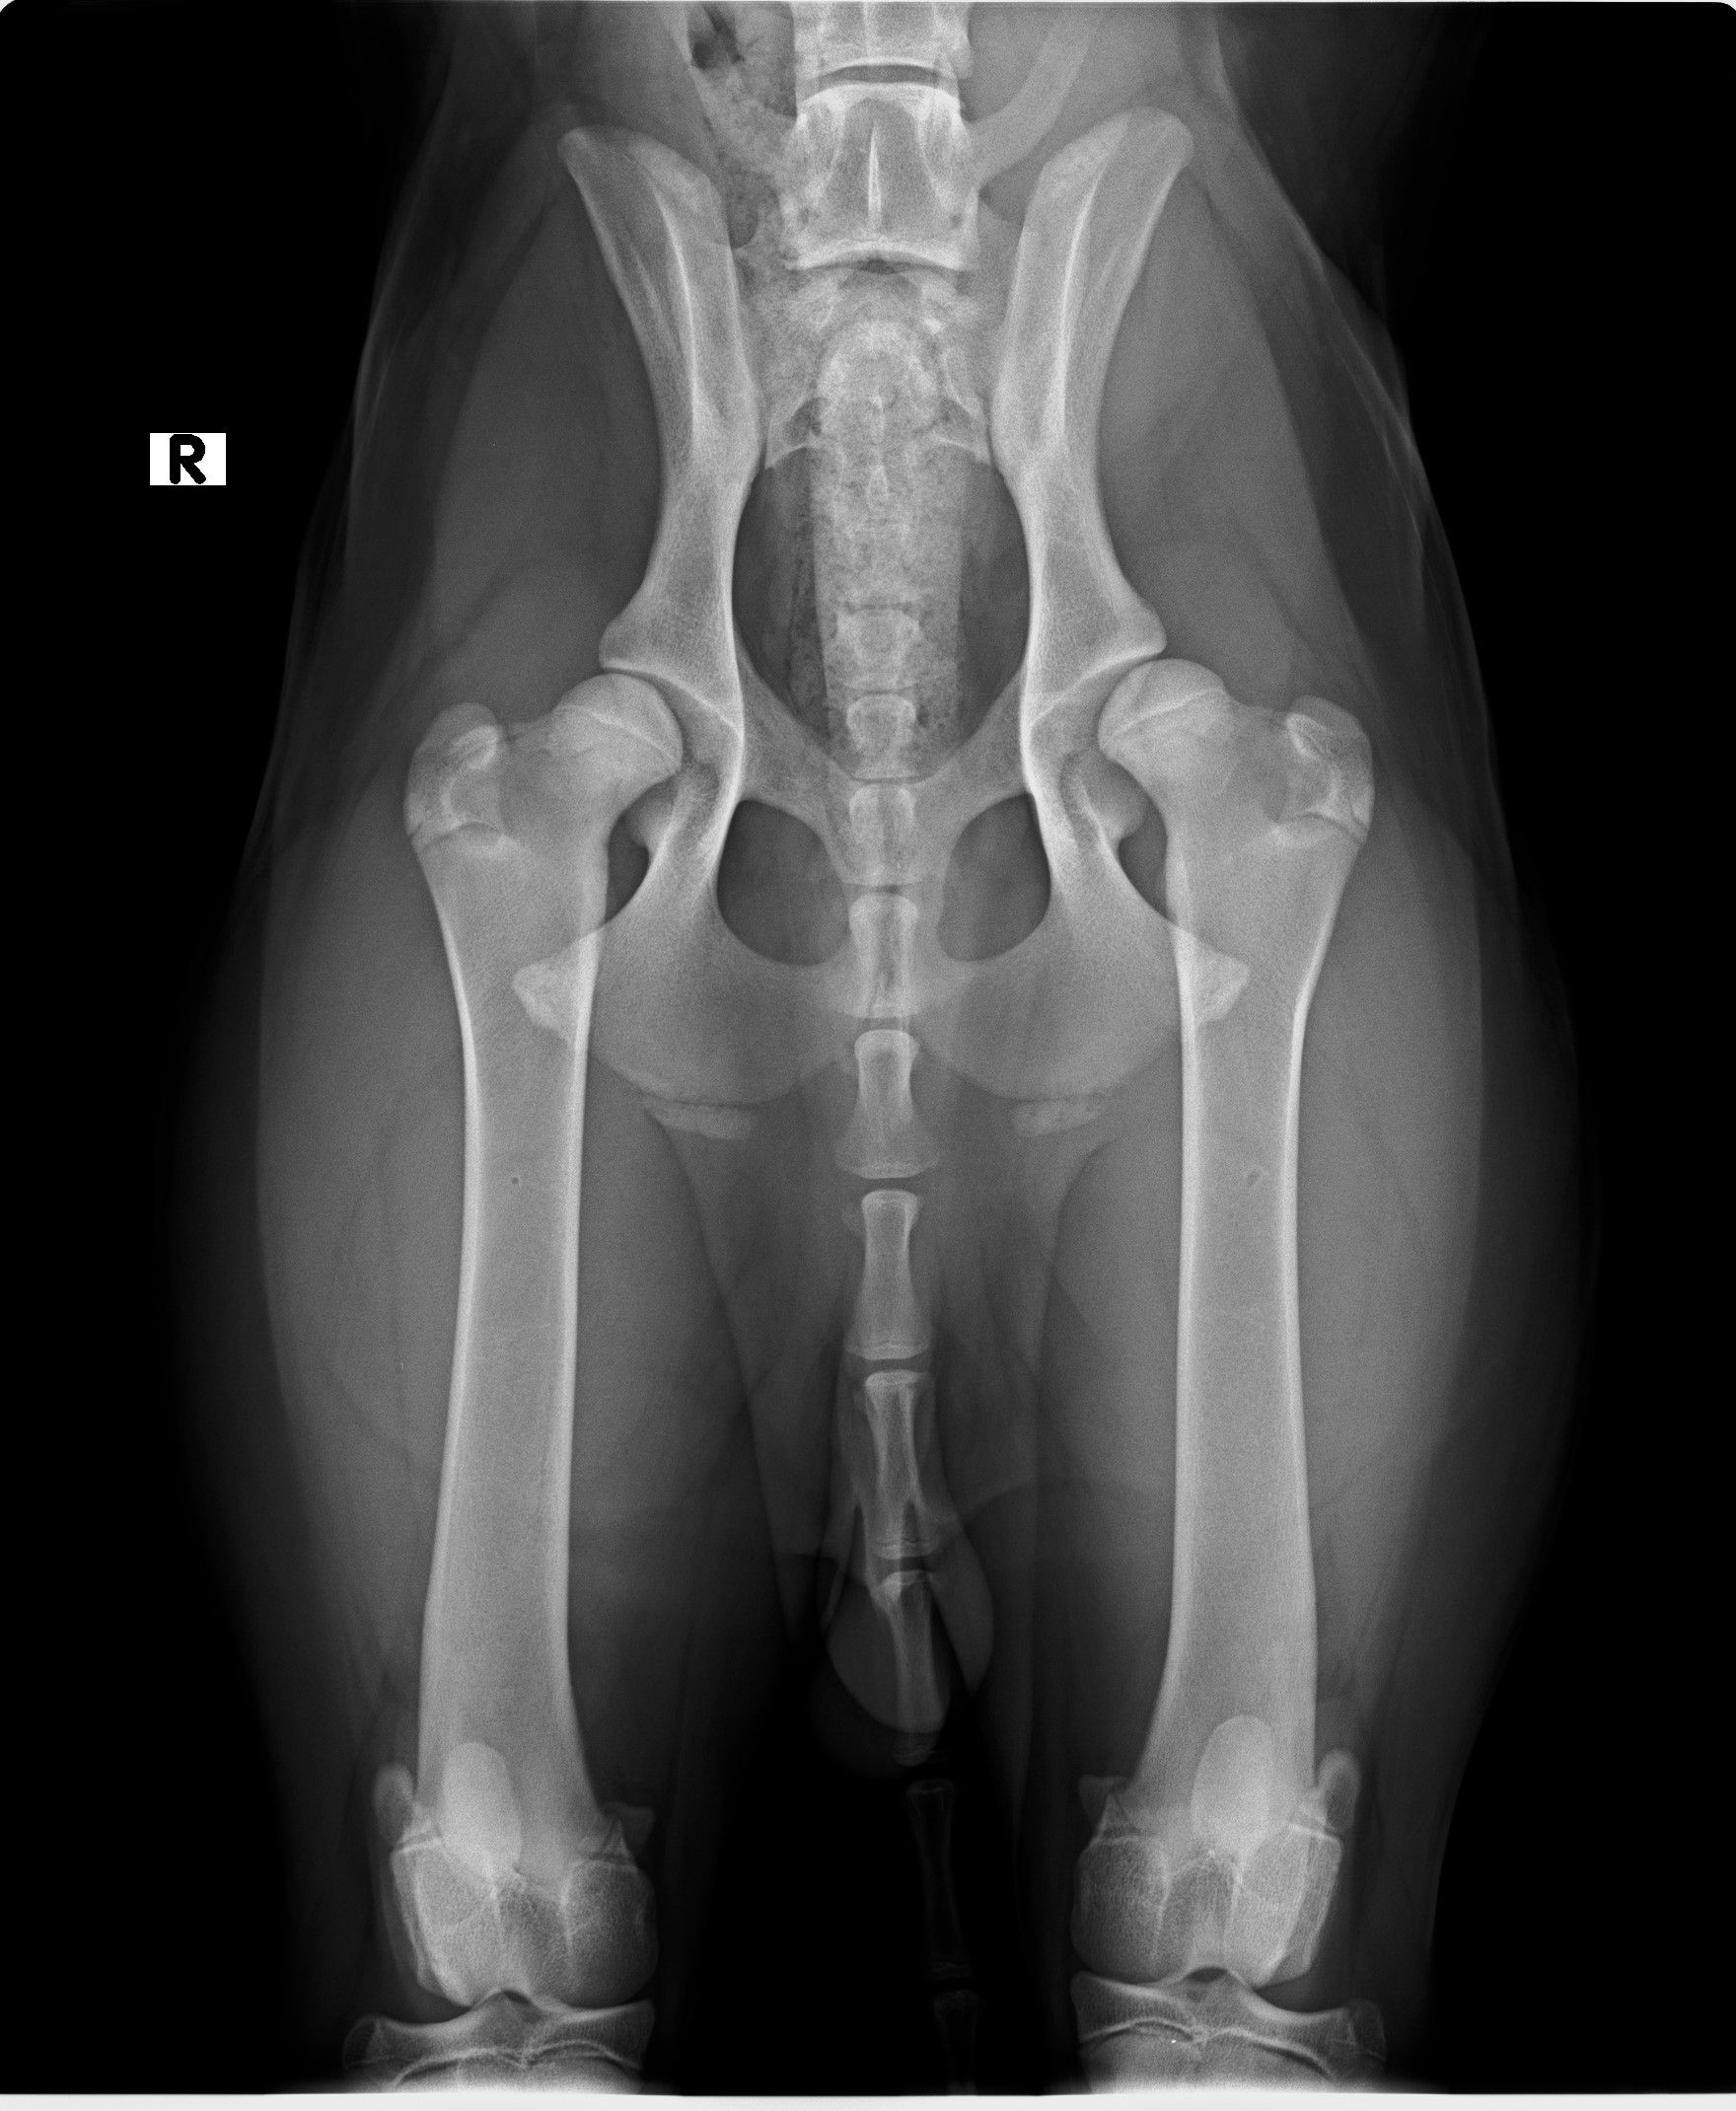

esame radiografico per displasia di anche e gomiti

DISPLASIA DELL'ANCA E GOMITO

La displasia dell'anca e del gomito sono malattie ereditarie che colpiscono i cani durante la crescita, causate da fattori genetici, ambientali, nutrizionali e traumatici, che alterano lo sviluppo articolare e portano a dolore, limitazione e artrosi.